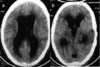

A 25-year-old man presented to a medical complaint with numerous neurologic signs and symptoms. These included a history of vomiting and headache, extraocular muscle deficits (CN 3 and 6), neck stiffness, and an intermittent fever. Imaging of his head was performed; see photograph.

LP had elevated CSF pressure. CSF examination showed cloudy fluid 150 cells/mm3 (normal lymphocytes 5% neutrophils. Protein was 180 mg/dl (normal 15-45 mg/dl), glucose was 58 mg/dl (50-75 mg/dl).

What was the most likely cause of the enlarged ventricles (lateral (both), 3rd, and 4th ventricles)?

A. Agenesis of the cerebral aqueduct

B. Blockage of both foramina of Monro

C. Cerebral abscess

D. Choroid cyst of the 3rd ventricle

E. Meningitis

E.

Meningitis

A 25-year-old man presented to a medical complaint with numerous neurologic signs and symptoms. These included a history of vomiting and headache, extraocular muscle deficits (CN 3 and 6), neck stiffness, and an intermittent fever. Imaging of his head was performed; see photograph.

LP had elevated CSF pressure. CSF examination showed cloudy fluid 150 cells/mm3 (normal lymphocytes 5% neutrophils. Protein was 180 mg/dl (normal 15-45 mg/dl), glucose was 58 mg/dl (50-75 mg/dl).

Diagnosed as meningitis. What would be the most likely cause of the meningitis?

A. Enterovirus (non-polio)

B. Mycobacteria tuberculosis

C. Neisseria meningitidis

D. Prion

B.

Mycobacteria tuberculosis